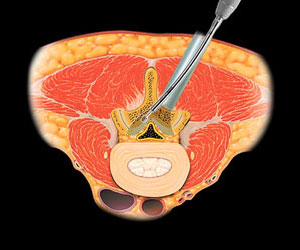

脊椎内視鏡手術

脊椎内視鏡手術とは、脊椎疾患に対して内視鏡を用いて、少ない侵襲で手術を行う方法です。

従来、骨や靭帯を切除して神経の圧迫を除去するために、内視鏡を用いることで必要最小限の切開で済むようになり、低侵襲の手術が可能になります。

全身麻酔下で、小切開を行い、内視鏡を用いて手術を神経モニタリングをしながら、神経を圧迫している骨や靭帯の切除、ヘルニアの摘出を行います。